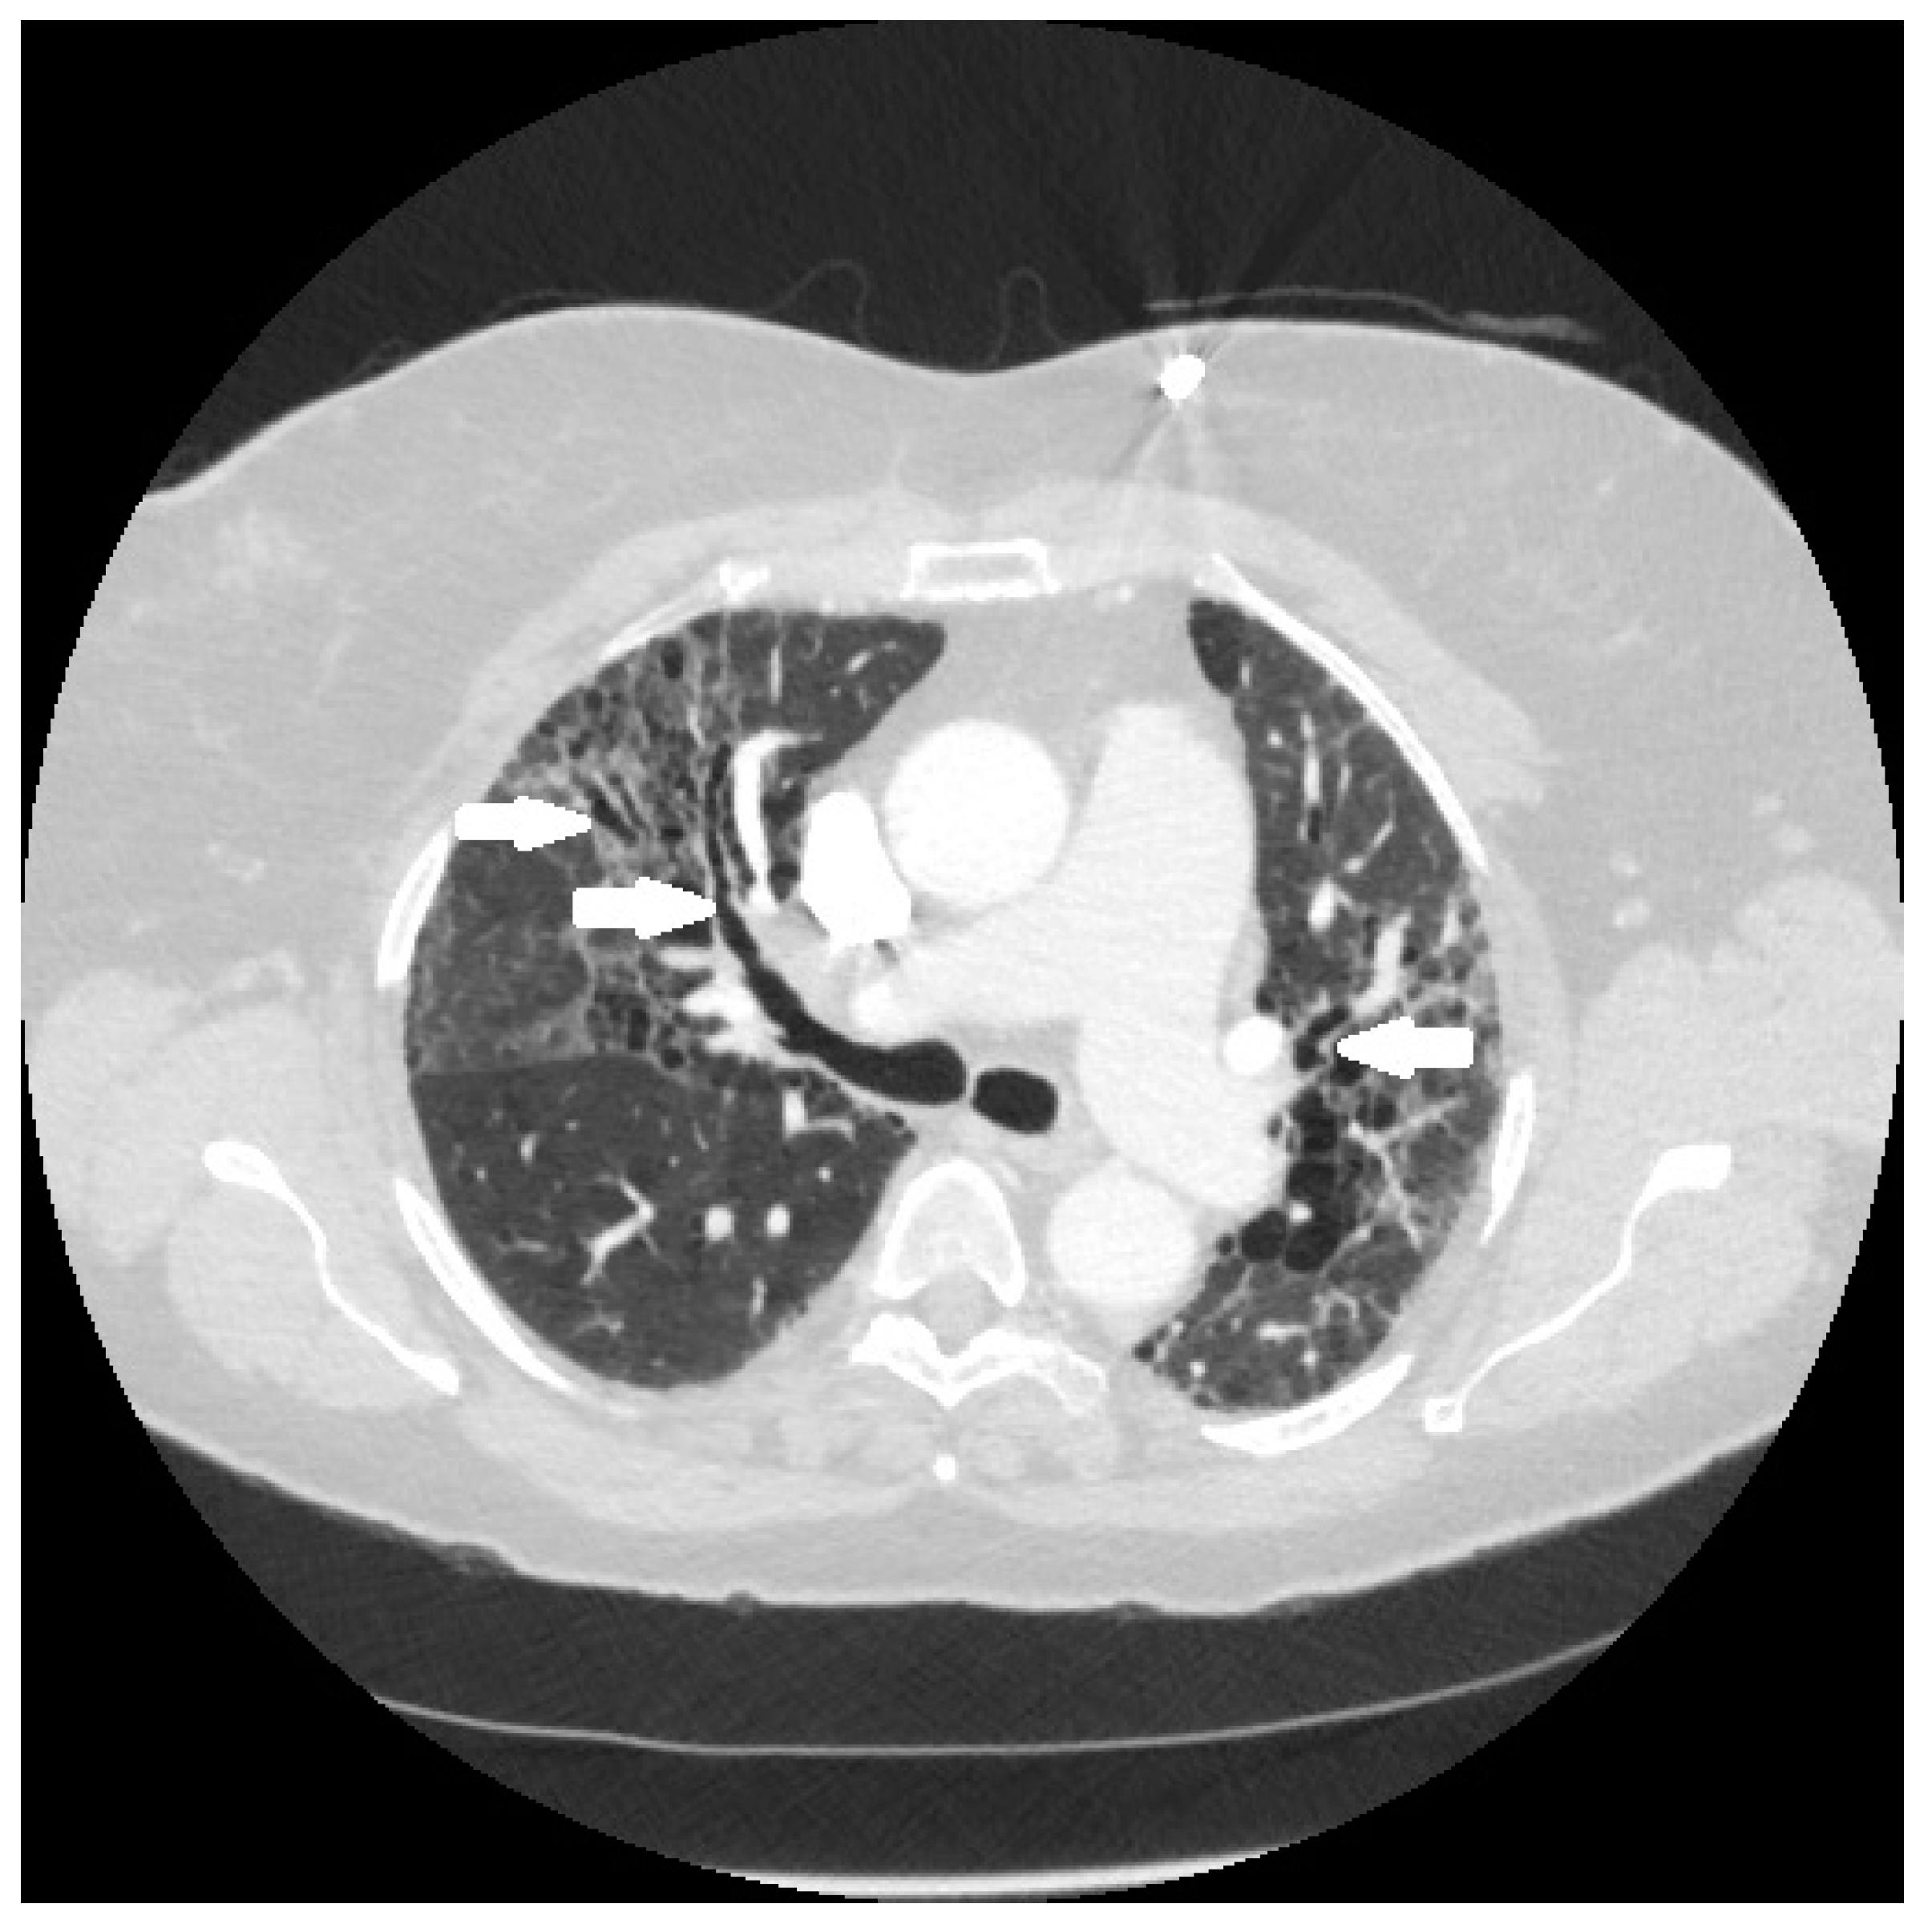

It is conjectured that the fibrosis in sarcoidosis is the result of granulomatous inflammation [68]. This conjecture is based on three lines of evidence. First, histological examination demonstrates that the majority of the fibrosis develops within or around the granuloma in so-called “hyalinized granulomas [69]. Second, pathological [69] and radiographic analyses [70] have shown that the fibrosis occurs predominantly in peribronchiolar locations, where sarcoid granulomas tend to form (Figure 8). Finally, the fibrosis often coexists with active pulmonary granulomatous inflammation on nuclear imaging studies [71].

Figure 8.

Chest CT scan of fibrotic pulmonary sarcoidosis. The fibrosis is typically in a peribronchial location, which in this case has resulted in fibrosis-induced traction bronchiectasis of airways (arrows).